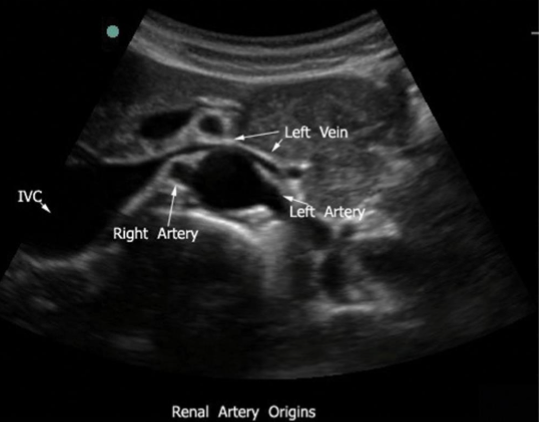

The left renal vein's unique anatomical course places it between which two arteries?

Superior mesenteric artery and the aorta

The left suprarenal vein and left gonadal vein typically drain into which vessel?

Left renal vein

Where do the renal arteries branch from the lateral wall of the aorta?

inferior to the SMA